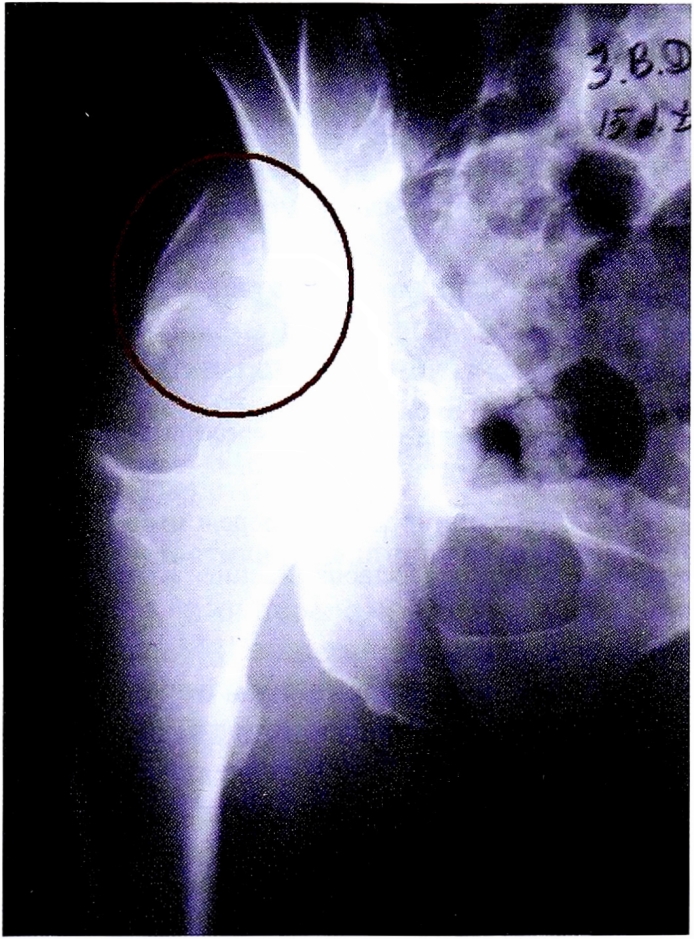

С помощью рентгенограммы в косой запирательной проекции, выполненной по методике НМИЦ ТО, диагностирован перелом задней стенки со смещением отдельного фрагмента. Также с помощью прицельного снимка определена целостность контуров запирательного отверстия (рис. 15).

Рис. 15. Рентгенография правого тазобедренного сустава в косой-запирательной проекции, выполнена по методике НМИЦ ТО. Стрелками показан перелом и отдельный фрагмент задней стенки.

Fig. 15. Obturator oblique view made with CITO method. Arrows shows separated posterior wall fragment.